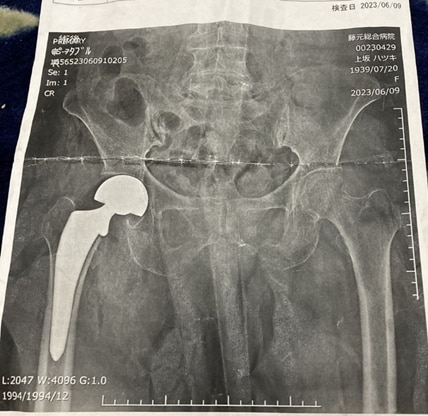

違う病院で、レントゲンを撮ると骨折。

その時の画像で、人工関節に置き換える判断をされたらしい。

(上は、自宅にあった紙焼きのレントゲンデータです。)